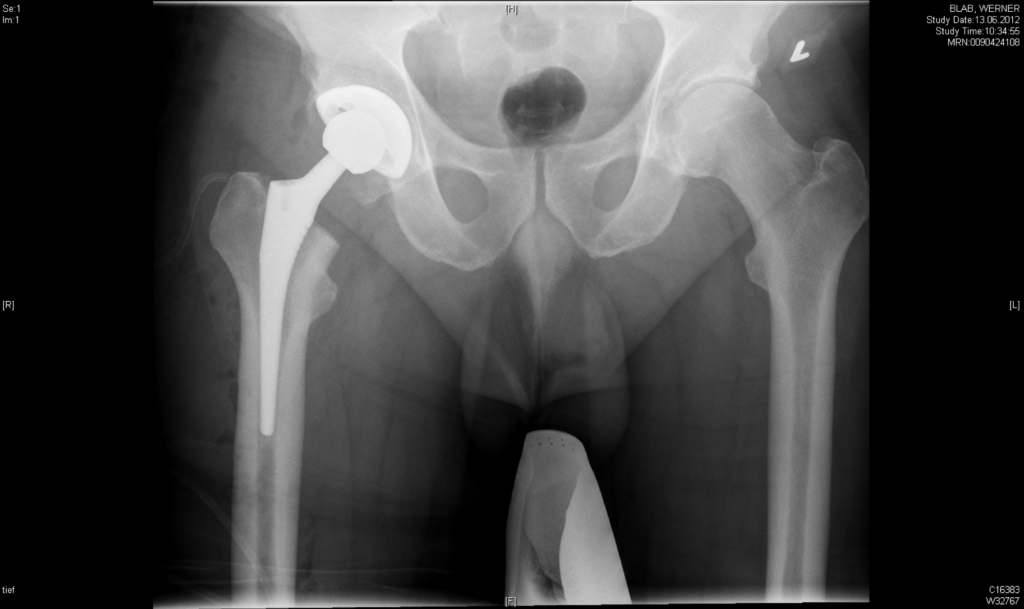

Dr. Rummel/Dr. Suren – Top Experten für Hüftendoprothetik favorisieren minimalinvasiven Zugang (MIS-Zugang – Modifizierter AMIS)

Künstliche Gelenke sind aus der modernen Medizin nicht mehr wegzudenken. Sie ermöglichen schmerzfreie Mobilität und steigern damit die Lebensqualität erheblich. Neben dem technischen Fortschritt sowie den besseren Materialien spielt aber auch die Operationsmethode eine große Rolle. So bevorzugen die Endoprothetik-Spezialisten PD Dr. Christian Suren und Dr. Christoph Rummel bei den Hüftprothesen den minimalinvasiven Zugang. Eine […]

Wechsel-Endoprothetik – warum ein Austausch eines künstlichen Gelenks?

Eine Revisionsoperation kommt in Frage, wenn eine Endoprothese an Knie, Hüfte oder Schulter nicht ausreichend gut funktioniert, nicht stabil genug ist oder sich aus dem Knochen gelockert hat. Betroffene Patienten beschäftigen vor allem Fragen wie „ist bei mir eine Revision notwendig?“, „wie verläuft eine Wechseloperation?“, „gibt es spezielle Risiken?“, „wie lange hält eine Revisionsendoprothese?“. Die […]